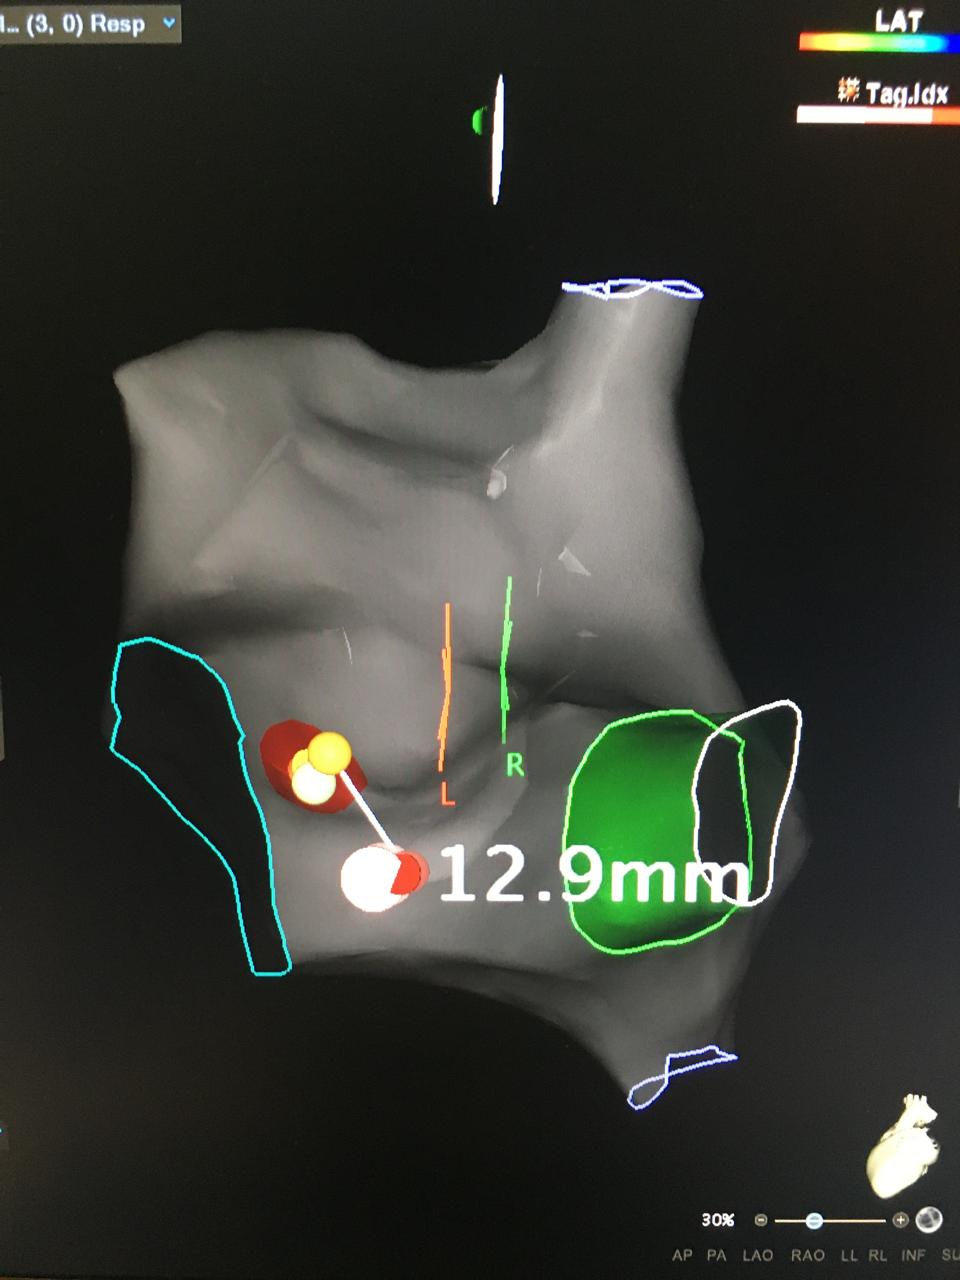

La taquicardia ventricular fascicular (TVF) es una forma rara de taquicardia ven...